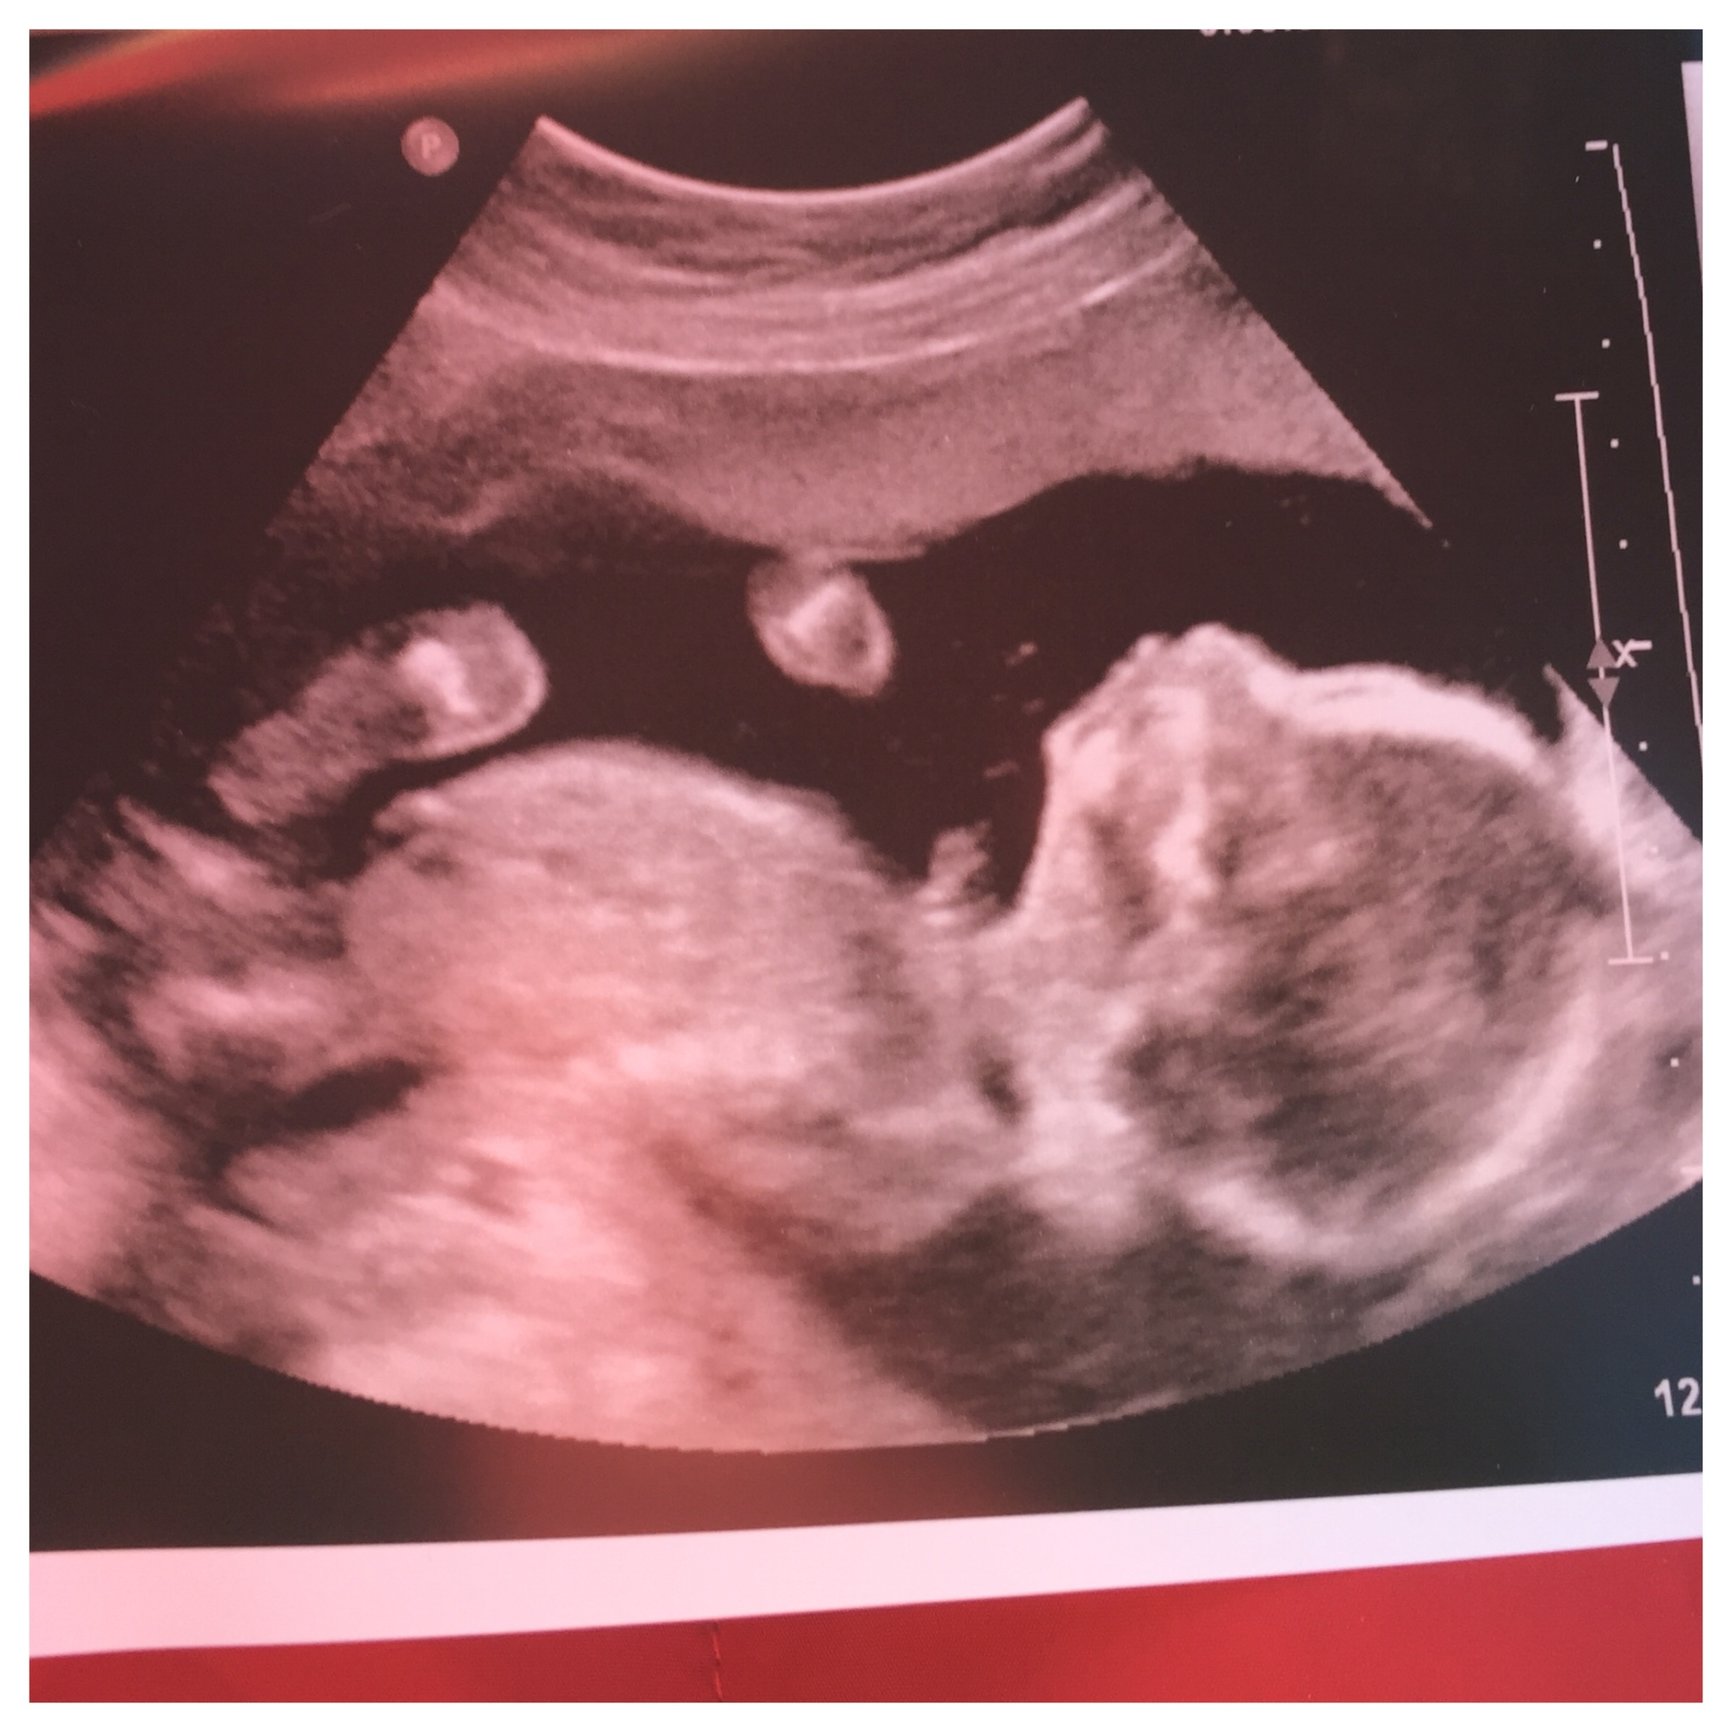

So we had our anatomy scan today! We are happy to learn that we are having a little girl! She is super active, and I could confirm that I was indeed feeling her crazy movements. Even the tech was surprised at just how much she was twisting and turning and flipping, lol. She apparently has a little cardiac abnormality- her aorta is arching to the right instead of the left, which they say will likely turn out to be a benign variant since everything else about her heart looks perfect, but we have appointments with a genetic counselor and a pediatric cardiologist set up for us, as well as lots of follow up growth scans. We are trying to focus on the good, she is growing perfectly and otherwise completely healthy and appropriate for her age. Hopefully we'll get more (good) answers after the echocardiogram with the cardiologist and put our minds at ease...

I love to read all of your stories and am so incredibly thrilled for each of you...I'm kind of a lurker, but I do keep up! I can't believe we are at this stage in our pregnancies!! We had our anatomy scan yesterday and our tech said everything is looking great and in even measuring a few days ahead! I couldn't be believe how much it was twisting and turning. We opted to not finding out the gender and wait until delivery. I'm such a control freak and it's killing me not to know, but I know the excitement of delivery will be so amazing. Who want some to take guesses on gender?! My friends and family are 70%girl 30%boy right now. See ultrasound below!